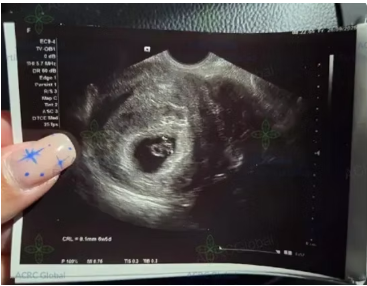

今週、赤ちゃんの力強い心音が確認されました!

妊娠アップデート:早期超音波検査で赤ちゃんの心拍を確認しました。当社では、小さなことから大きなイベントまで、日々の状況をお知らせします!